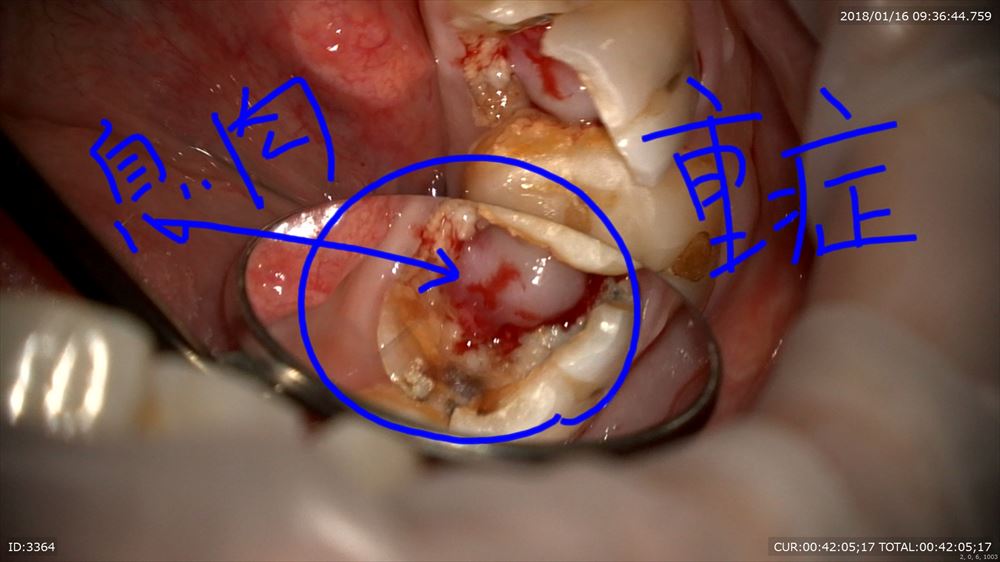

この方はまだ若いのに重度の虫歯を放っておいてこんなになってしまいました。

皆さん虫歯は絶対に放置しないでください。こんな状態になってしまいます。明らかに保存は難しそう。

歯科ドックを行い徹底的に調べました。すると一筋の光が。息肉を丁寧に除去。

イスムスの整理や基本の感染源を徹底的に除去(無痛)

1時間の格闘。4根すべて開通し根管形成まで終了。

術前と比較してみましょう

患者さまと2人で喜びました。あとは次回最終的なお薬をいれます。根管治療2回で終了予定。

きちんと歯科ドックで病態を診断し、最新治療を行い基本に忠実に治療を行えば救える歯も多数あります。